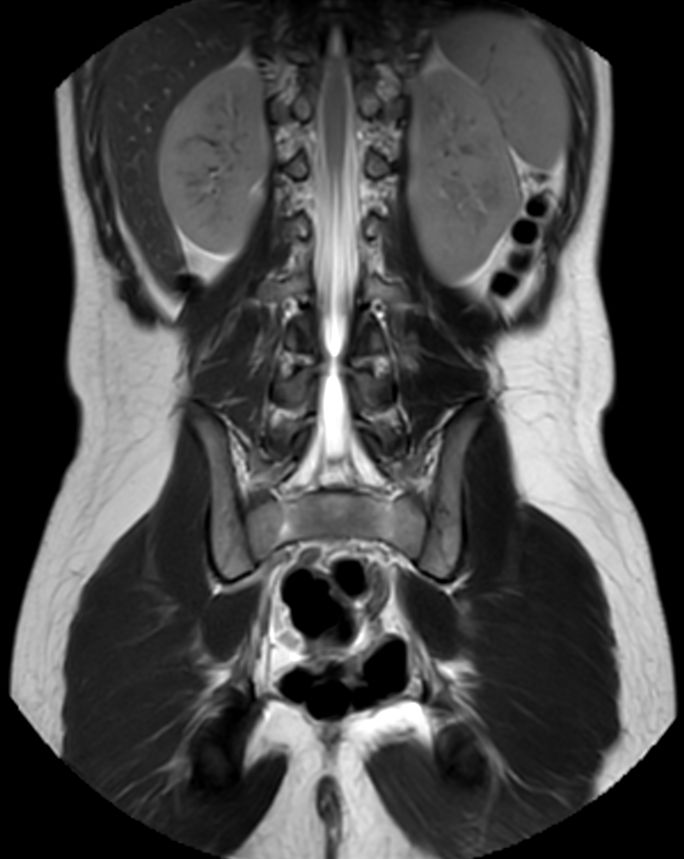

8 years old pediatric patient with a fistula in the pelvis. MultiVane XD is used to achieve high resolution diagnostic images, even in the case of severe patient motion. Integration of Compressed SENSE acceleration technique enables speeding up of the entire exam.

Coronal T2w TSECompressed SENSE